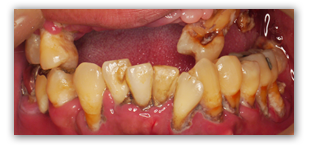

なんだこれは!と思われるかもしれませんが、これは重度の歯周病にかかった患者さんの口の中の写真です。上の歯はほとんど抜け落ち、残っている下の歯も歯石まみれでグラグラです。忙しかったり、痛みがなかったのでまあいいかと20年来歯医者にいかないまま放っておいたら、前歯が抜けてしまって見た目がかっこ悪いということで来院されました。

え?痛くないの?と思いませんか?実際患者さんに尋ねてみると、腫れたりして痛い日もあったけど、だいたい次の日にはなんともなくなったので大丈夫だと思ったとのことでした。

この中で虫歯は非常に小さいものがたったの2本だけ。歯周病は虫歯のような痛みがでにくいので、患者さんが気づかないままどんどん進んでしまう恐ろしい病気なのです。